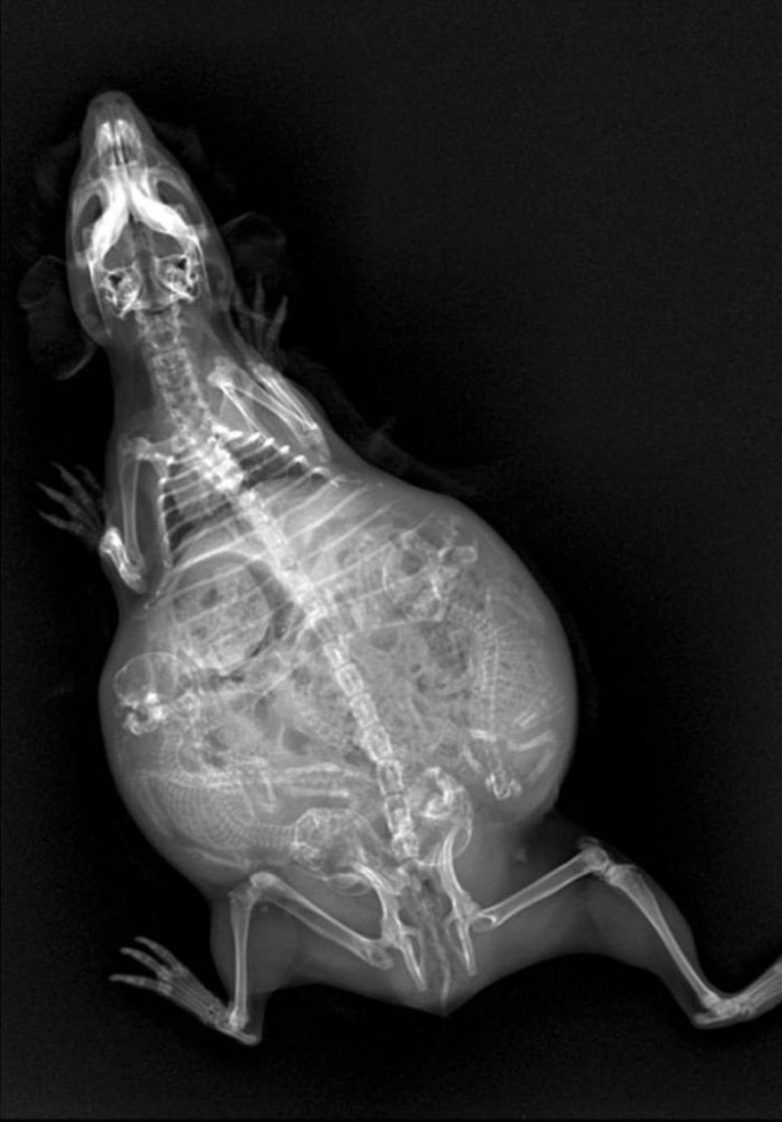

Беременность животных на рентген-снимках

Представляем вашему вниманию серию интересных рентгеновских снимков, на которых можно рассмотреть, как располагаются будущие детеныши енота, летучей мыши или, скажем, бородатой ящерицы в животах их мам.

Летучая мышь